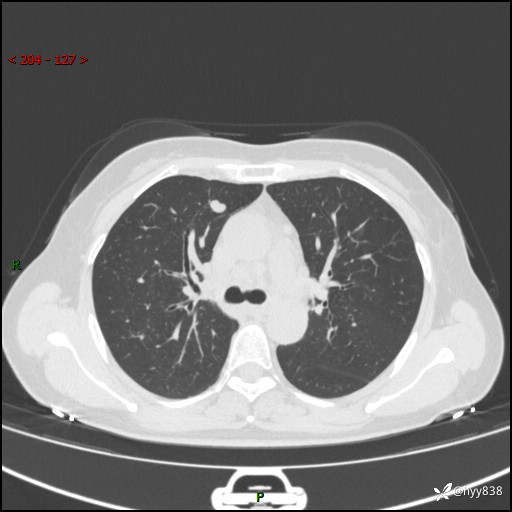

【患者信息】:58岁/女

【主诉】:体检发现肺结节

【检查】:胸部CT平扫+增强